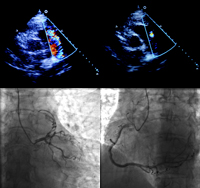

超声心动图:左房增大(3.84 cm),余房室内径(-),LVEF(-),室间隔增厚(1.3 cm),肺动脉长轴切面可见收缩、舒张期一束蓝色异常血流自根部进入肺动脉,最高流速491 cm/s,肺动脉内径(-)。

冠脉造影:冠脉供血呈右优势型,左主干未见明确病变,LAD管壁不规则,三支冠脉未见明显狭窄。LAD对角支远端和RCA屈曲、延长,并可见两者至肺动脉的造影剂充填,LAD中段可见肌桥,收缩期狭窄60%,前向血流TIMI 3级。

超声心动图发现肺动脉内异常连续血流,疑诊冠脉-肺动脉瘘。冠脉造影证实这一诊断。